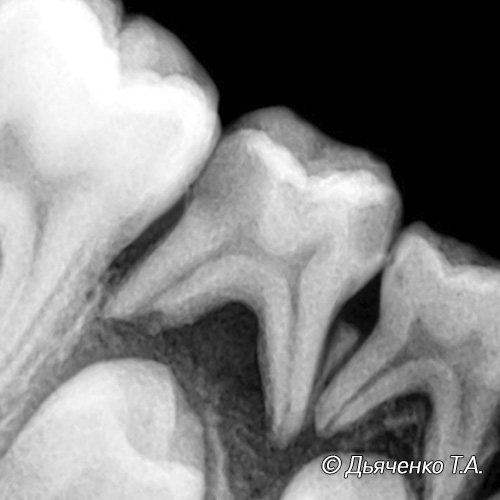

Если помощь ребенку не оказана, далее инфекция начинает распространяться из полости зуба в корневые каналы. Разрушается ткань сосудисто-нервного пучка (пульпы), воспаление при длительном течении приводит к отмиранию (некрозу) тканей. Все это может способствовать развитию периодонтита либо в хронической форме, либо острой в результате гнойного расплавления пульпы.

Это длительно существующий хронический воспалительный процесс в зубе и околозубных тканях.

Так как инфекция даже при хроническом течении проникает в периодонт, чем длительней процесс, тем сильнее разрушение тканей. Возникает боль при накусывании на зуб, часто пульсирующая.